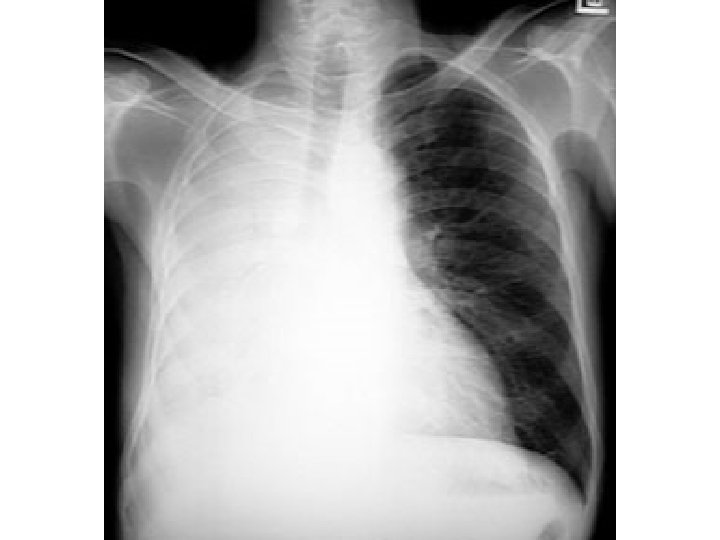

Air in pleura Atelectatic lung Hemithorax Mediastinual shift Pneumothorax